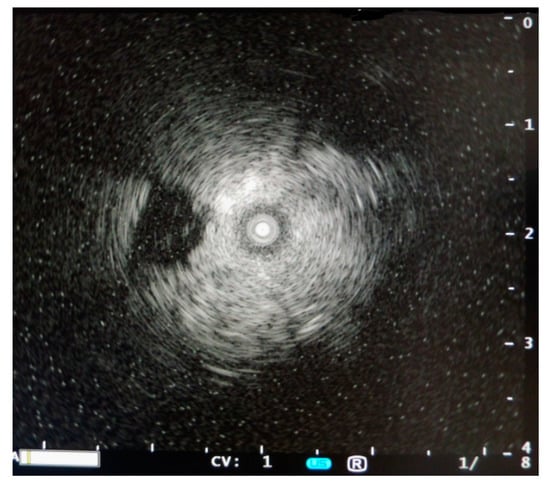

Later work investigated PFC filling in vivo by Lesser et al. [18] using porcine models and Degnan et al. [19] in infants. In these undertakings, visualization of central structures was not found and sonography appear as white lung syndrome with low penetrability in absence of A Lines (Figure 2). Table 2 summarizes the literature with corresponding sonographic finding of a PFC filled lung.

Figure 2. Sonographic image of the lung during static PFC administration in infants showing white lung between the rib shadows without the visualization of lung structure and absence of A-lines. (With permission from Degnan et al. [19]).